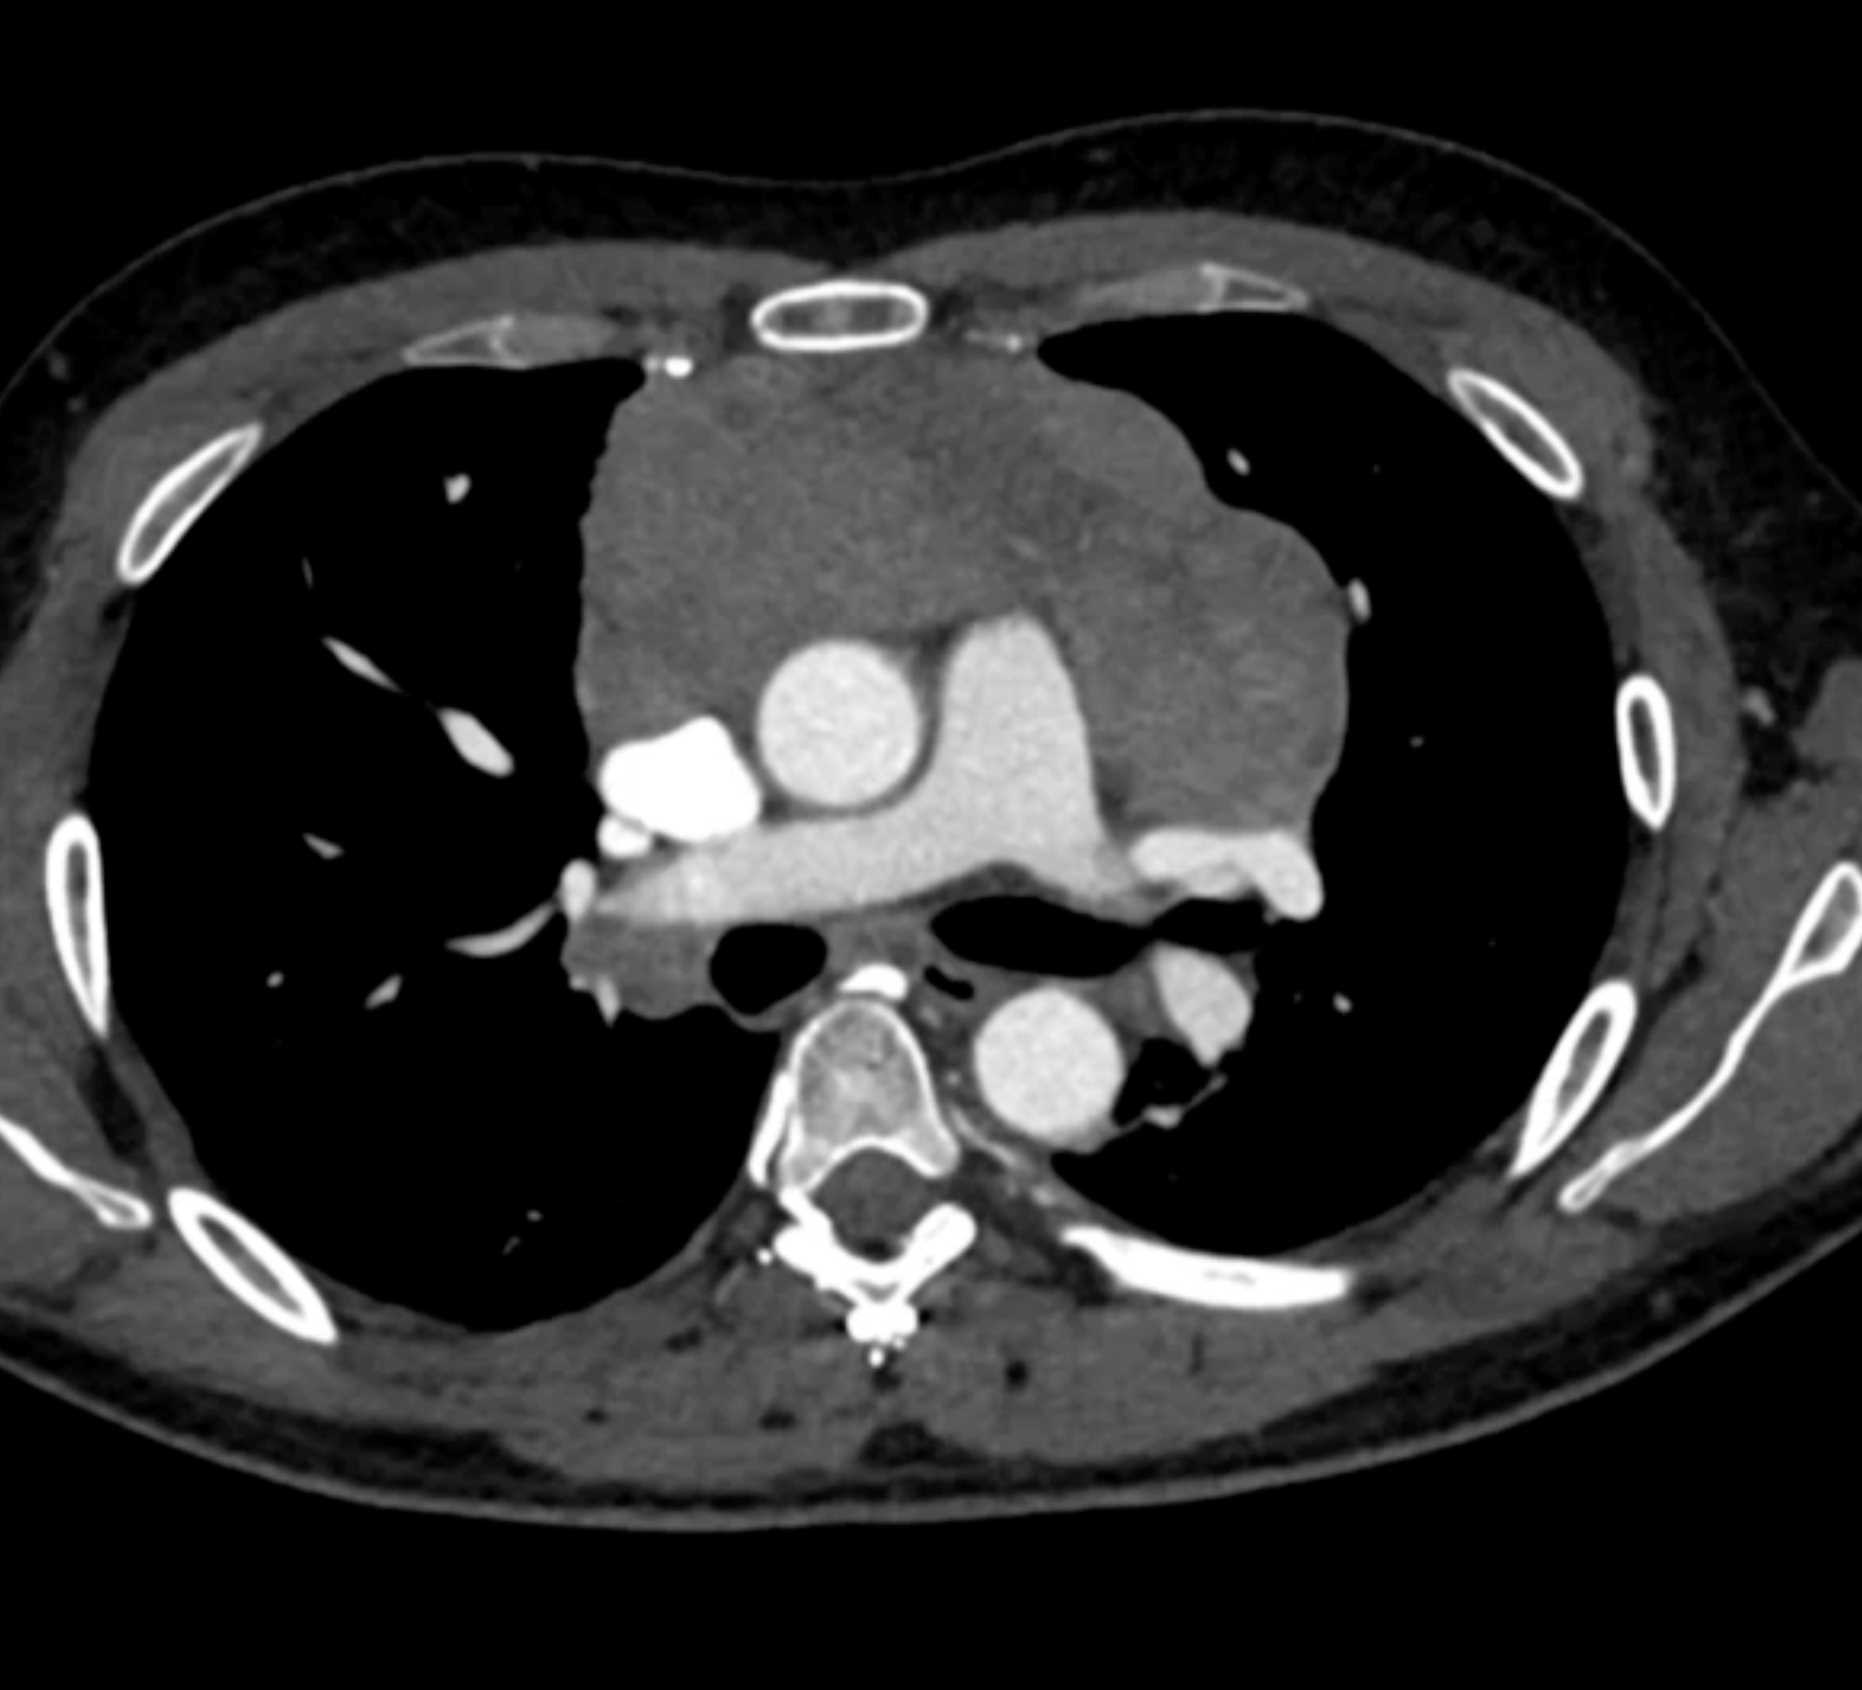

Thymic Carcinoma